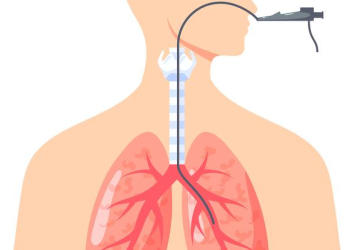

支氣管鏡是一種細(xì)長(zhǎng)的、柔軟的、可彎曲的管狀儀器,它通過鼻腔或口腔插入,經(jīng)過咽喉、氣管,最終到達(dá)支氣管。支氣管鏡上配備有光源和攝像頭,能夠?qū)⒑粑纼?nèi)部的影像實(shí)時(shí)傳輸?shù)斤@示屏上,讓醫(yī)生清晰地觀察氣管和支氣管的管壁、管腔以及周圍組織的情況。支氣管鏡檢查是呼吸系統(tǒng)疾病最重要的診療手段。對(duì)于慢性咳嗽、痰中帶血、肺癌、肺結(jié)核、肺炎等診療評(píng)估,阻塞性肺炎、異物吸入、肺不張等疾病是首選診療措施。支氣管鏡檢查痛嗎?目前,我院開展的支氣管鏡檢查分為普通支氣管鏡檢查、無痛支氣管鏡檢查兩種。普通支氣2025-09-15